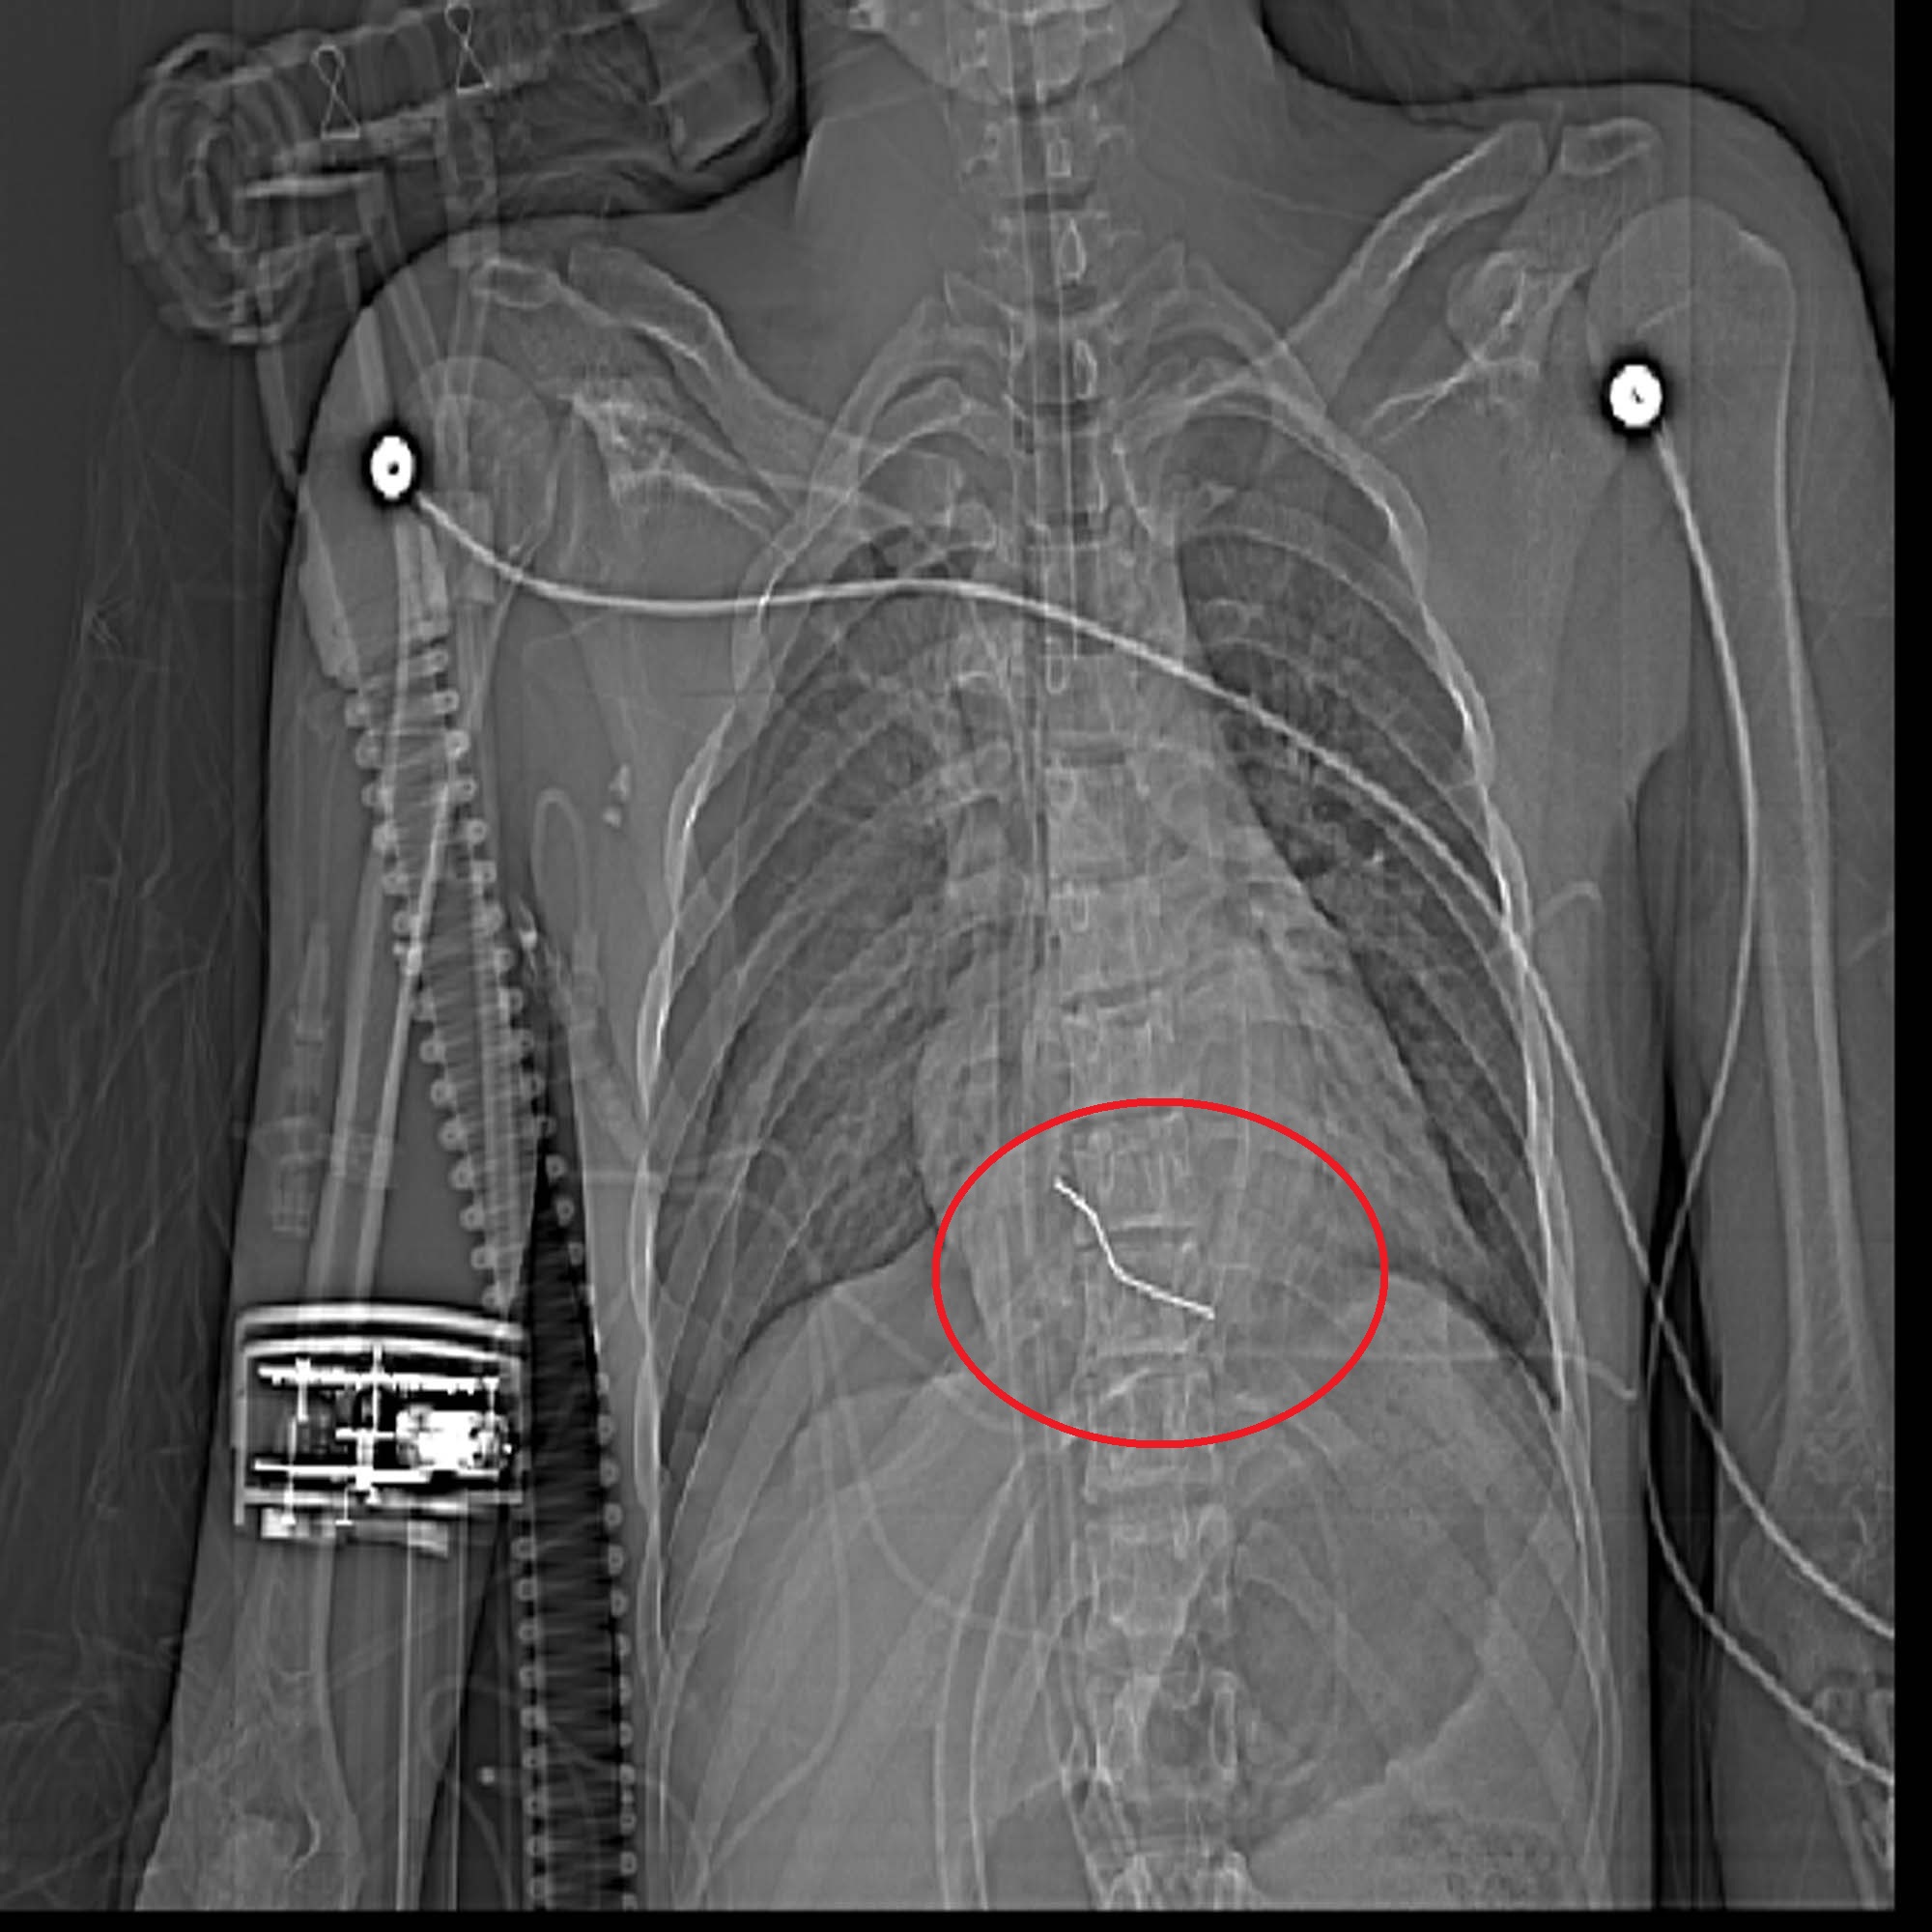

خارج کردن میخ 5 سانتیمتری از قلب پسرجوان سبزواری

روابط عمومی بیمارستان تخصصی و فوق تخصصی حشمتیه از نجات جان بیمار بعد از خارج کردن میخ 5 سانتیمتری از قلب بیمار خبر داد.

به گزارش روابط عمومی بیمارستان حشمتیه دکتر راستی ریاست بیمارستان حشمتیه عنوان کرد: 23 خرداد ماه ، ساعت 22:00 جوان 21 ساله  به دلیل فرو رفتن میخ به ناحیه قفسه سینه و قلب وی از شهر داورزن  به بیمارستان حشمتیه  منتقل شد.

وی افزود:  بیمار در هنگام ورود به بیمارستان  دچار کاهش هوشیاری و افت شدید علایم حیاتی بوده است و در حالت احیای قلبی و ریوی سریعا به بخش اتاق عمل منتقل می گردد و تحت عمل جراحی قرار می گیرد. خوشبختانه تیم جراحی قلب این بیمارستان به سرپرستی دکترعبدالرحمن جراح قلب همچنین متخصص بیهوشی قلب دکتر یوسفی ، پزشک متخصص داخلی قلب  دکتر اسماعیلیان وتیم اتاق عمل قلب در یک عمل جراحی 1.5 ساعته اقدام به بازکردن قفسه سینه و خارج کردن میخ از قلب این بیمار می نمایند..

دکتر عبدالرحمن با بیان این نکته که با توجه به شرایط بیمار نیاز فوری به انجام عمل جراحی بوده است گفت میخ 5 سانتیمتری  از سمت چپ استخوان جناغ بیمار وارد و به بطن راست قلب آسیب وارد کرده بود.بعد از باز شدن قفسه سینه  ،بعلت عدم حرکت قلب  با انجام ماساژ باز قلب تا ضربان قلب برگردد. بعد ازترمیم ناحیه پارگی و خارج کردن میخ قفسه سینه بیمار بسته شد و بیمار به بخش مارقبت های ویژه قلب باز منتقل گردید..

دکتر راستی در ادامه گفت که بیمار با هوشیاری کامل  و وضعیت عمومی بسیار مطلوب بعد از پنج روز تحت مراقبت بودن 28 خرداد مرخص گردید.